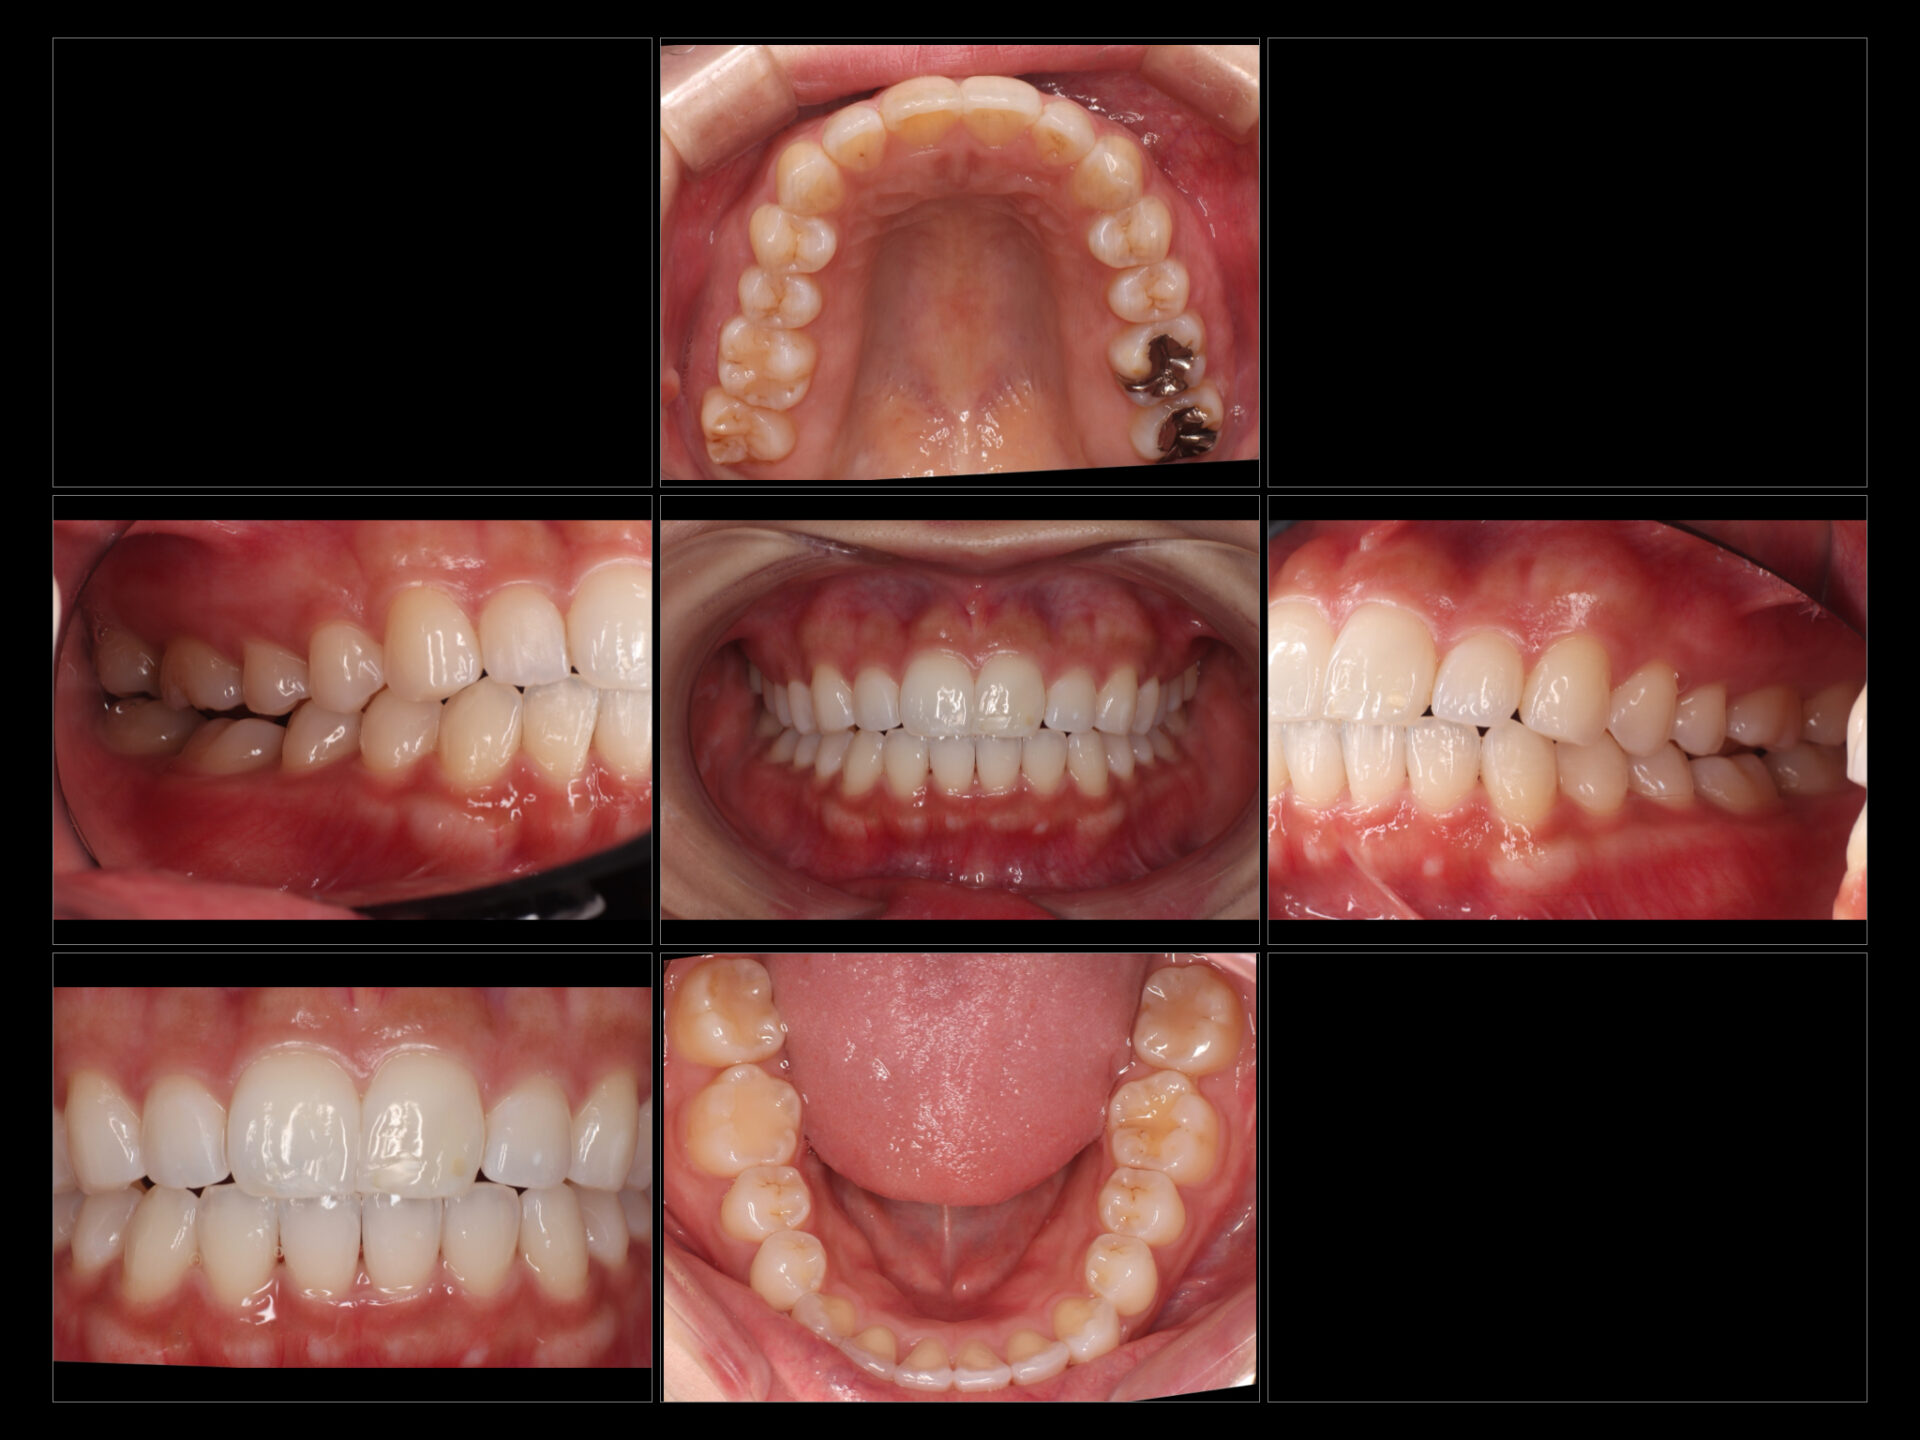

2. Before / After(画像)

3. 治療内容・結果

歯列矯正: マウスピース型矯正装置を用い、1年という期間でスムーズに歯並びを整えました。

ホワイトニング: 矯正治療の進捗に合わせ、ホワイトニングを実施。歯並びだけでなく歯の色調を明るくすることで、治療完了後の満足度がより高まりました。

口元の変化: 歯並びが整ったことで、下顔面(口元)のバランスが改善され、より洗練された印象になりました。